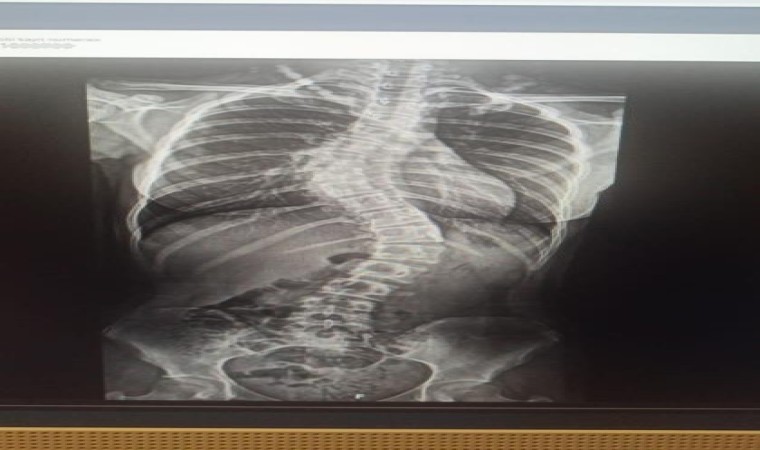

Samsun’da yaşayan ve bir süredir skolyoz hastası olan 10’uncu sınıf öğrencisi Zeynep Pehlivan, tedavi için Antalya Memorial Hastanesi Ortopedi ve Travmatoloji Bölümünden Doç. Dr. Ömer Bozduman’a ulaştı. Yapılan görüşmelerin ardından Pehlivan ve ailesi Antalya’ya davet edildi. 4 gün önce Antalya’ya gelen Zeynep Pehlivan için ameliyat kararı alındı. Ameliyatla genç kızın sırtında ve belinde bulunan eğrilikler enstrümantasyonlu bir sistemle füzyon cerrahi tedavisi yaparak düzeltildi. Ameliyatın hemen ardından bir gün sonra yürümeye başlayan Pehlivan, 4 gün sonra taburcu edildi.

Zeynep’in skolyoz hastalığından dolayı uzun zamandır takiplerinde olduğunu belirten Doç. Dr. Ömer Bozduman, “Rahatsızlığı gerilemek yerine ilerleme olunca müdahale etmeye karar verdik. Ameliyatını gerçekleştirdik. Sırtında ve belinde olan eğriliklerini enstrümantasyonlu bir sistemle füzyon cerrahi tedavisi yaparak düzelttik. Ameliyattan sonra birinci gün yürüttük. Problem yaşamadık, dördüncü gün taburcu edeceğiz. Zeynep’in en sık hareketlenmelerinin olduğu boyun sırt bileşkesine beliyle kalça bileşkesine dokunmadık. Daha az hareketsiz olan sırt bölgesine füzyon cerrahi yaptık. Bundan sonra çok fazla bir fonksiyon kaybı olacağını düşünmüyoruz” dedi.